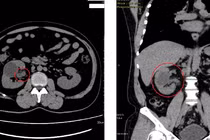

Bệnh sỏi thận có diễn biến âm thầm, người mắc bệnh sỏi thận có thể không nhận ra cho tới khi đi khám. Nếu không được phát hiện và điều trị kịp thời thì rất có thể sẽ dẫn tới biến chứng suy thận.